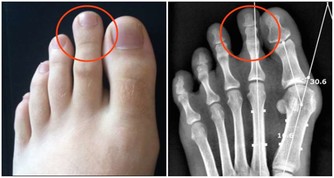

2. 肺:

理論上肺從20 歲就開始衰老。有些人到了40 歲,會開始氣喘吁籲。

這是因為控制呼吸的肌肉和胸腔變得僵硬起來,使呼吸相對於從前困難一些。